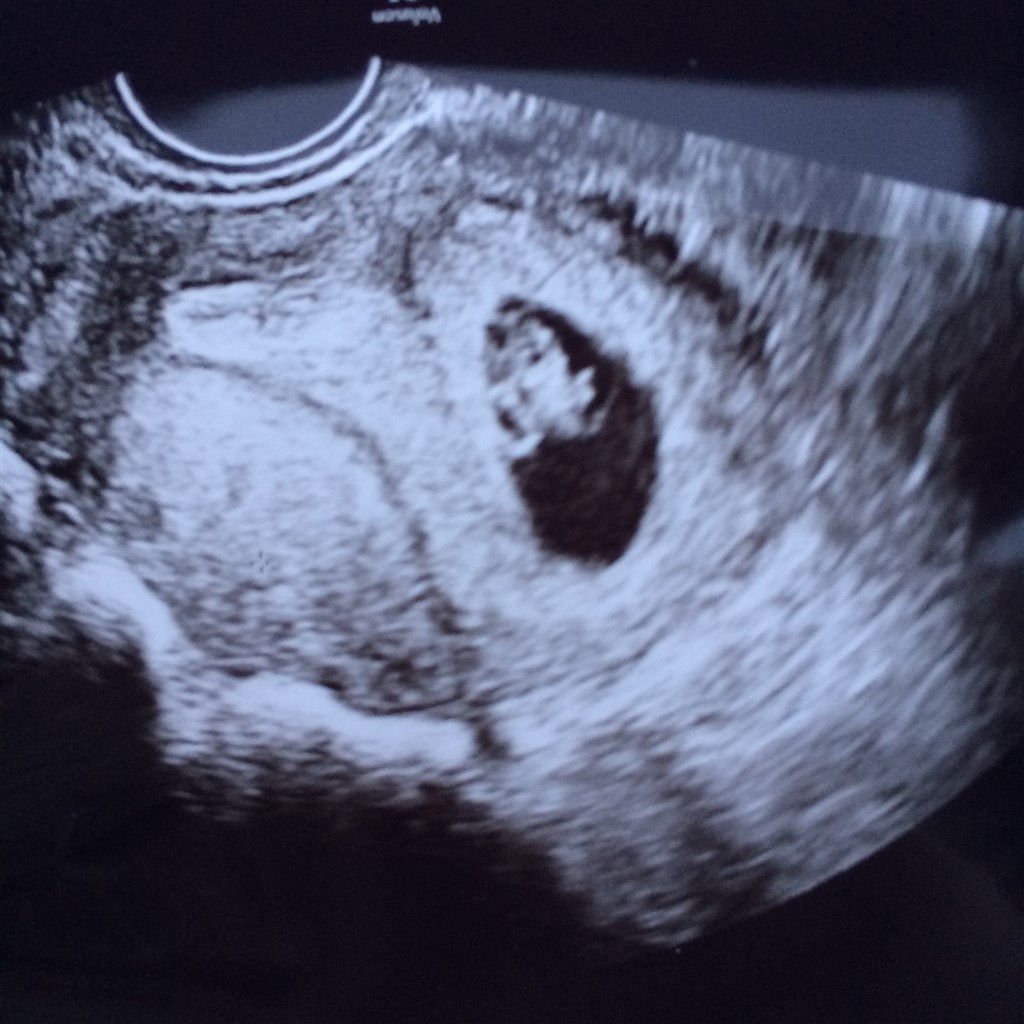

Idag er vi afsluttet i fertilitets regi .

det lille hjerte slog og spiren målte 11mm

er Idag 7+4